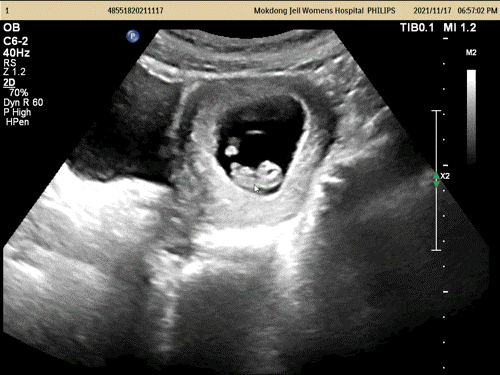

증상은 생리 전의 증상과 거의 비슷해서, 임신이라고는 생각하지 않았다…!배나 가슴, 허리의 통증 정도…?오늘 내일 생리 시작할 줄 알았어.4주 6일 아기집 확인

4주 6일 병원에 가서 아카짱의 집을 확인!10주까지는 질 초음파로 봐 주실 예정.심장 소리를 들을 때 모자수첩을 받기로 했고, 산전검사 결과 갑상선 수치가 경계선에 있어서 갑상선 수치 검사도 그때 같이 하기로 했다!